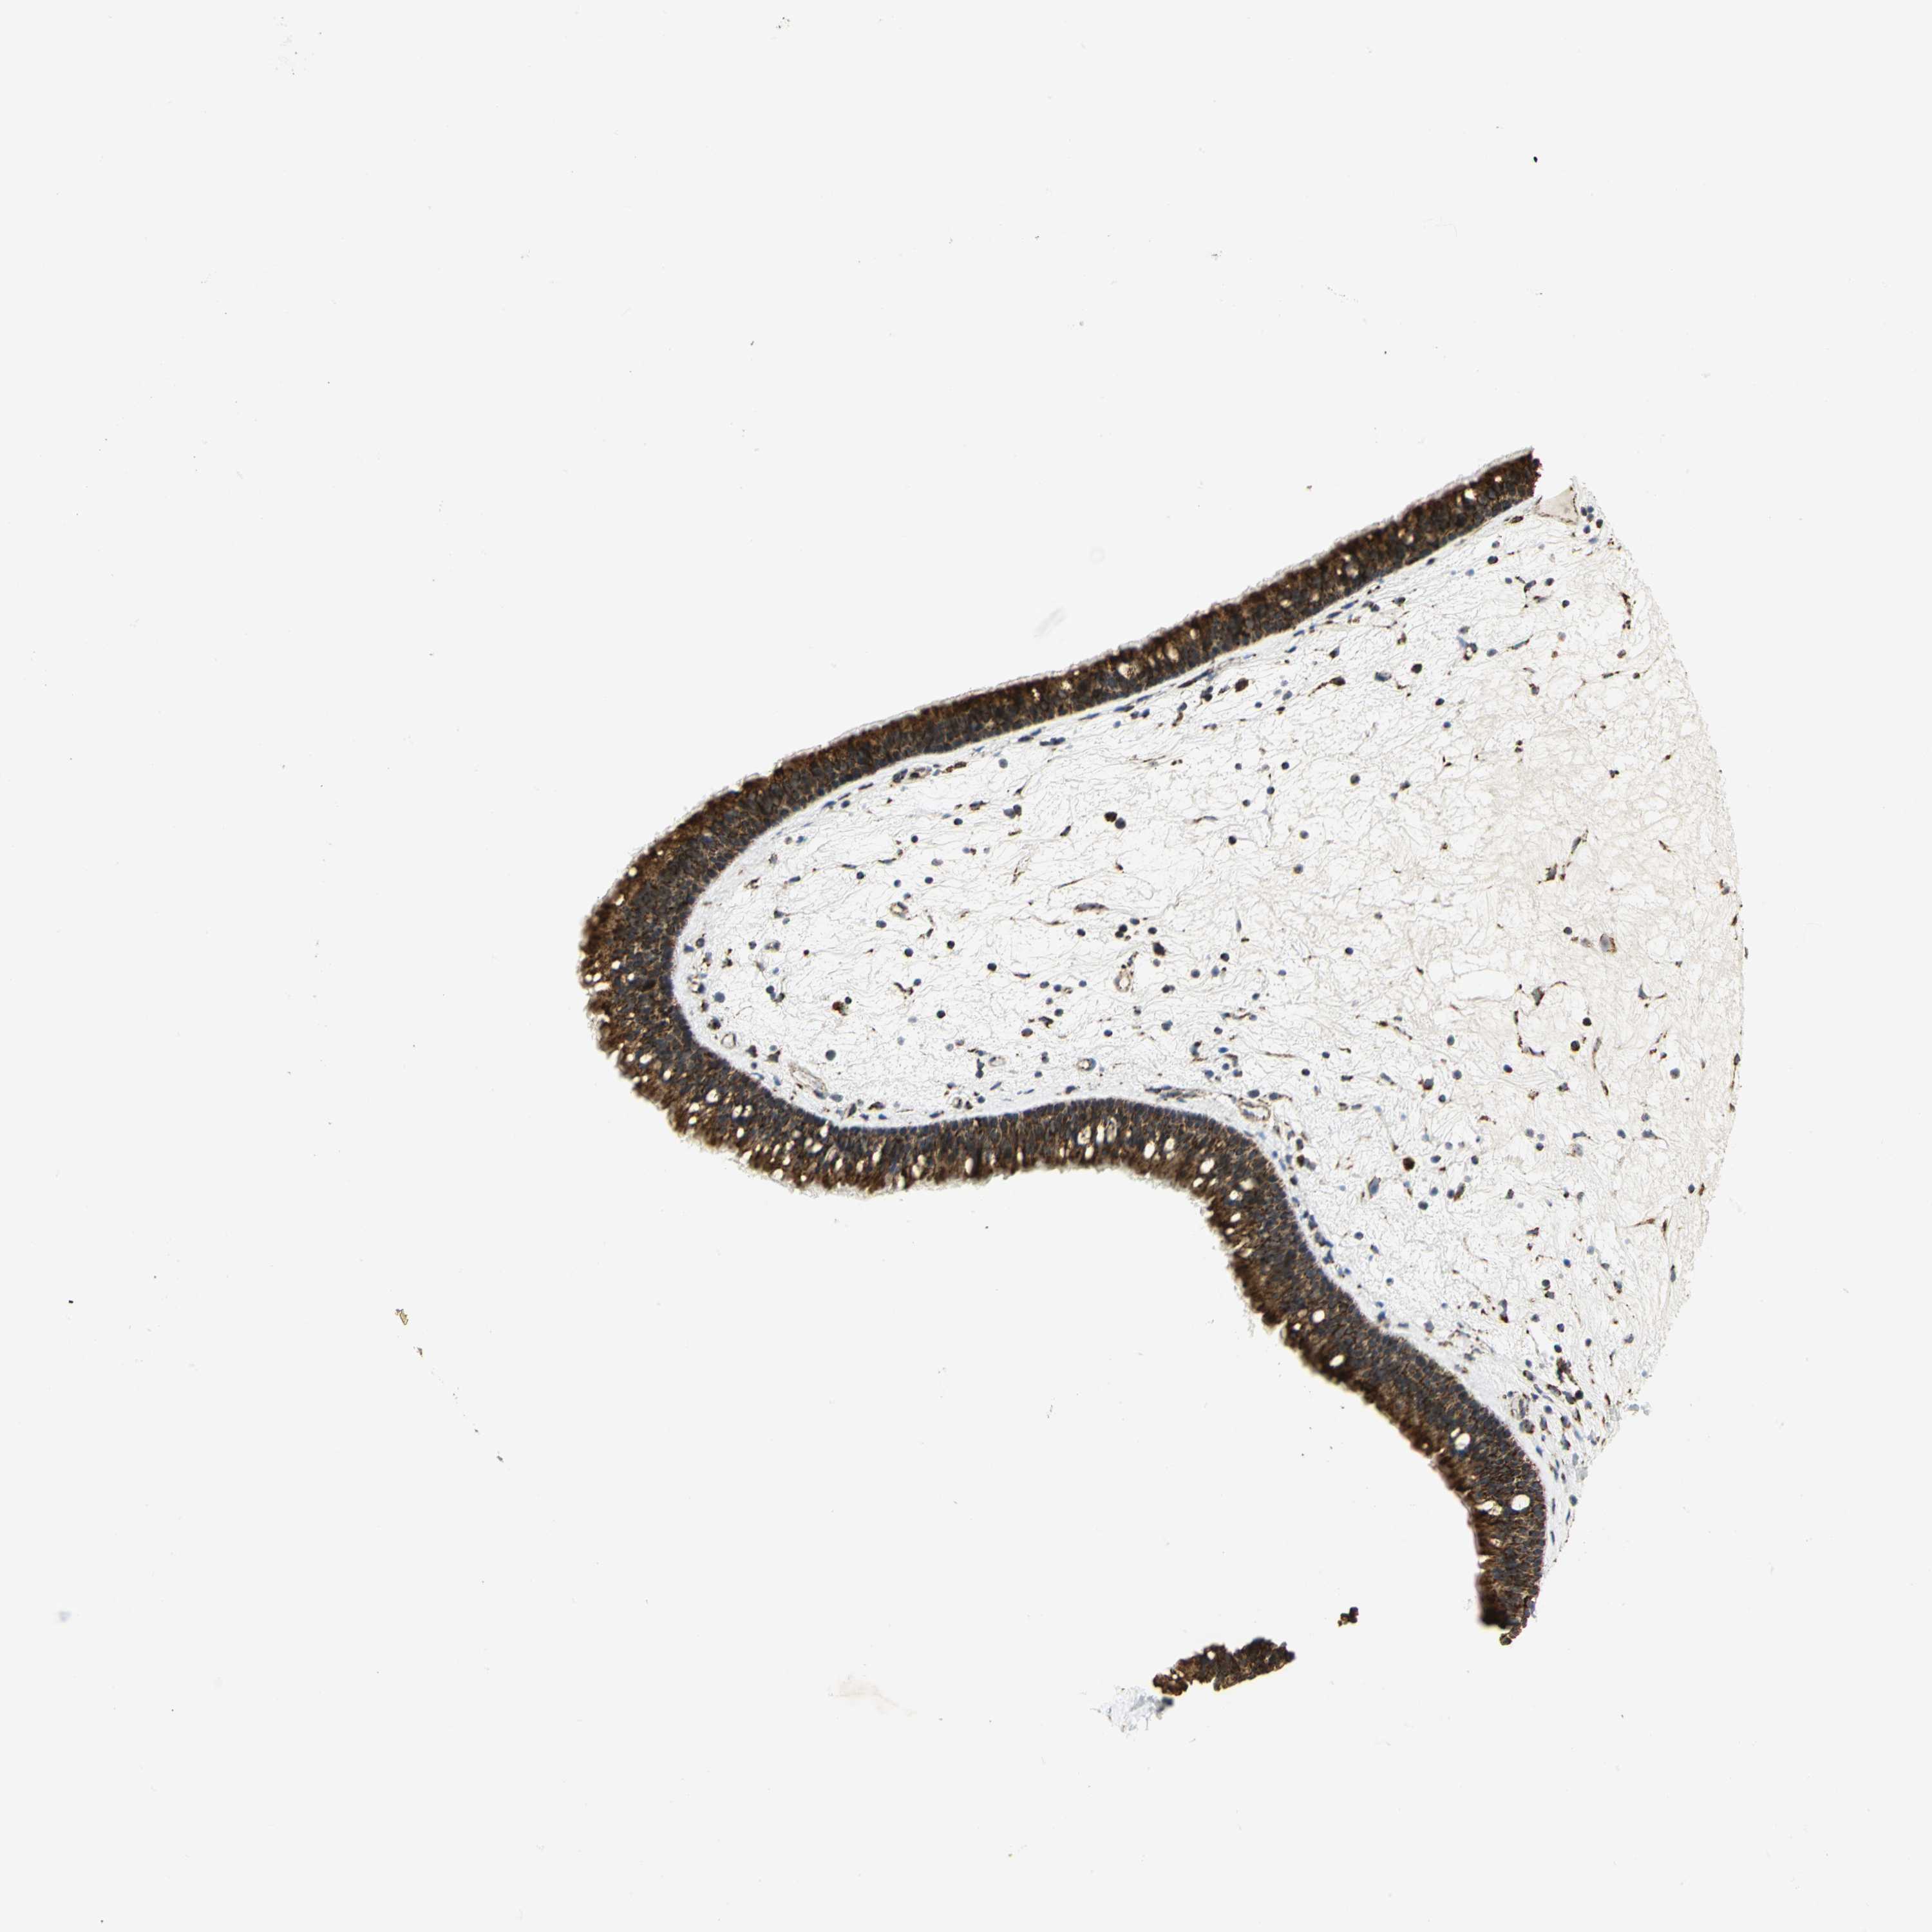

NASOPHARYNX - Antibody stainingi

Antibody staining in the annotated cell types in the current human tissue is reported as not detected, low, medium, or high, based on conventional immunohistochemistry profiling in selected tissues. This score is based on the combination of the staining intensity and fraction of stained cells.

Each image is clickable and will lead to virtual microscopy that enables deeper exploration of all samples and also displays staining intensity scores, fraction scores and subcellular localization as well as patient and tissue information for each sample.

Antibody HPA030780Antibody CAB005885Antibody CAB072343

Respiratory epithelial cells HighHighHigh